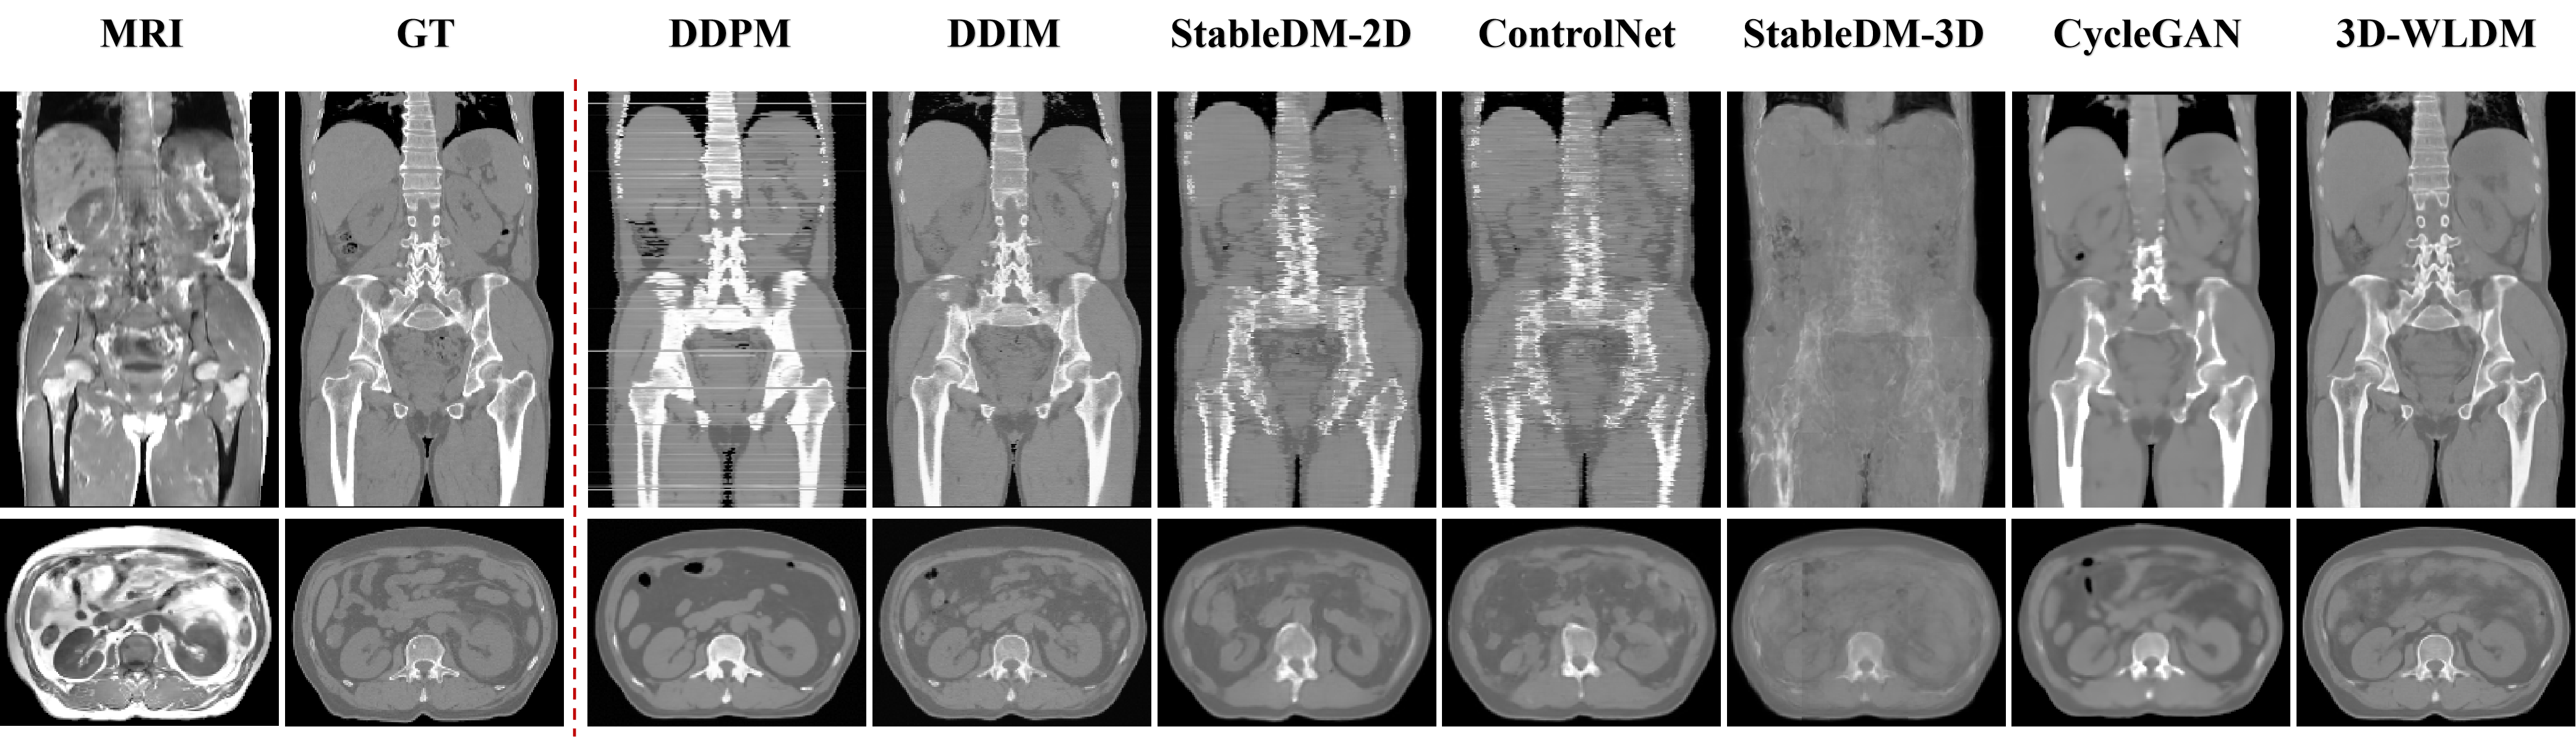

We performed MR-to-CT modality translation experiments to benchmark the proposed 3D Wavelet Latent Diffusion Model (3D-WLDM) against several state-of-the-art baselines, including DDPM [41], DDIM [39], StableDiffusion 2D (StableDM-2D)[37], ControlNet[34], StableDiffusion 3D (StableDM-3D)[37], and CycleGAN[42]. Representative qualitative comparisons are illustrated in Fig. 5.

In 2D transverse slice generation, DDPM occasionally produces failed outputs, notably horizontal line artifacts in coronal views. Our experiments suggest that DDPM is highly sensitive to the initial noise vector, resulting in substantial variability in output quality. These artifacts are attributed to the model’s limited generative capacity. Increasing the number of diffusion steps reduces such interslice inconsistencies but further exacerbates inference inefficiency, underscoring the trade-off between quality and computational cost in DDPM. DDIM improves upon DDPM by enhancing sampling efficiency and reducing interlayer artifacts. Nevertheless, noise artifacts persist, particularly in transverse-plane reconstructions, suggesting suboptimal structural fidelity.

StableDM-2D and ControlNet generate CT images with visually realistic textures and intensity distributions that closely resemble ground truth. However, both suffer from anatomical misalignment. Structural discontinuities are evident, particularly in axial and coronal planes. These inconsistencies stem from limitations in the variational autoencoder (VAE) decoder, which, while enhancing perceptual quality, degrades structural integrity during latent encoding. The cross-attention mechanism in StableDM-2D and the condition fusion strategy in ControlNet both fall short in enforcing spatial coherence. StableDM-3D amplifies these limitations, yielding overly smooth and anatomically imprecise reconstructions, highlighting the current challenges faced by 3D diffusion frameworks in preserving high-fidelity structural information.

CycleGAN exhibits pronounced anatomical inconsistencies, especially in spinal structures, likely due to ambiguous MR signal characteristics. As a bidirectional generative framework, it tends to propagate non-physiological features introduced by low-contrast MR inputs. These artifacts degrade the fidelity of CT synthesis and compromise structural accuracy.

In contrast, our proposed 3D-WLDM demonstrates marked improvements in both visual fidelity and anatomical coherence. The integration of Wavelet Blocks enhances multiscale encoding and reconstruction, while the Structure-Modality Disentanglement module mitigates inconsistencies in latent space representation. Furthermore, the DSCA module significantly improves the generation of fine structural details during the diffusion process. Together, these components enable 3D-WLDM to produce CT reconstructions that are not only visually compelling but also structurally faithful to the underlying anatomy.

Quantitative results also reveal important discrepancies between visual quality and structural fidelity across baseline methods. For instance, DDIM generates visually sharper images in the coronal plane (Fig. 5) compared to StableDM-2D and ControlNet, yet achieves lower SSIM and higher MAE. This contrast is attributed to differences in generative pathways: latent vector–based decoding via variational autoencoders (VAEs) typically enhances perceptual quality and contrast but may fail to preserve accurate anatomical detail when compared to pixel-space diffusion outputs.

CycleGAN achieves the highest SSIM and lowest MAE among baseline methods, despite clear structural deficiencies, such as vertebral blurring and discontinuities (Fig. 5). This performance is primarily due to its strong contrast preservation and capacity for global structural consistency. However, its failure to reconstruct fine bone structures limits its clinical utility – particularly in applications such as PET/MR attenuation correction, where accurate bone delineation is critical due to its high electron density and poor visibility in MR imaging.

In contrast, 3D-WLDM delivers state-of-the-art performance across all quantitative and qualitative assessments. Its combination of multiscale wavelet encoding, structure-modality disentanglement, and enhanced structural attention enables improved anatomical fidelity, contrast consistency, and noise suppression. These properties underscore the model’s potential for clinical translation, particularly in scenarios demanding high-resolution, structure-preserving CT synthesis.